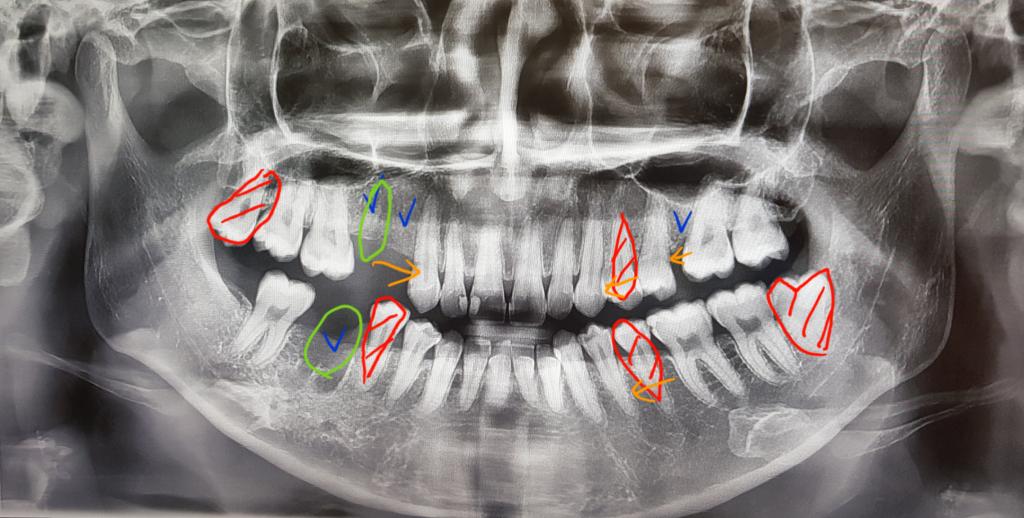

치아교정 및 임플란트 질문입니다..

진작 빨리 치료를 했어야했는데 정말 여기저기 다니면서 고민만 하다가 시간이 훌쩍 지나버렸어요 교정 방법이 너무 다른데 제 치아가 너무 어려운(?) 케이스 같아서.. 부작용+외모변화 등 걱정이 많습니다 사실 임플...

전문의 답변 1